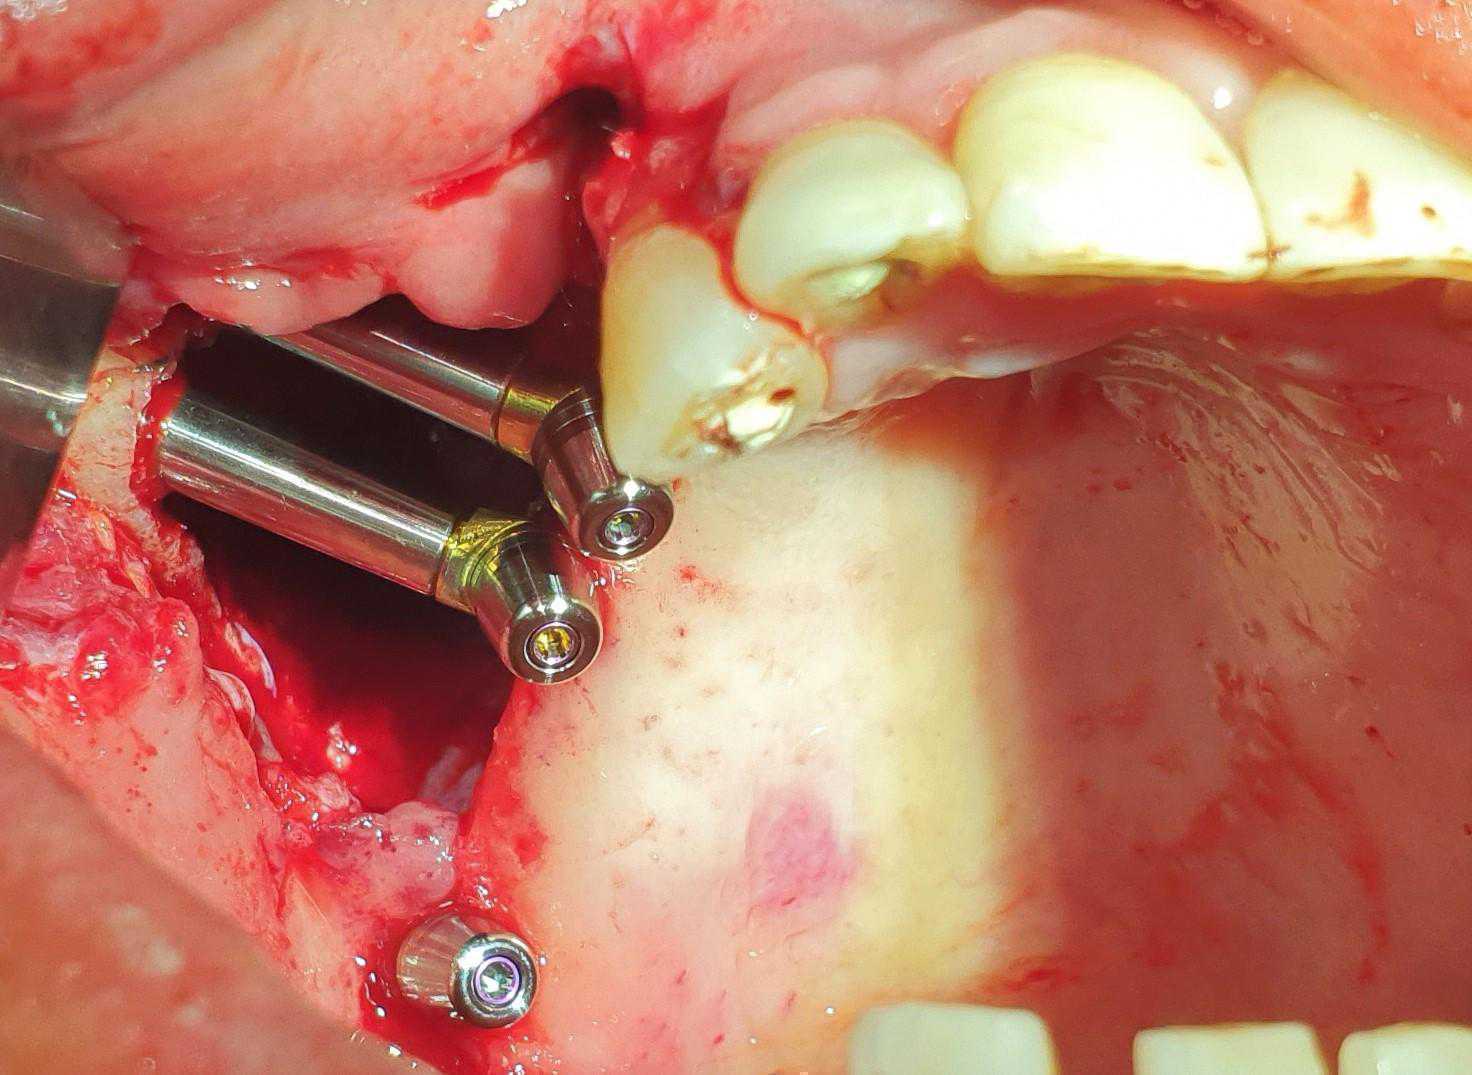

https://demo.discussdentistry.com/forums/topic/post-mucormycosis-avascular-necrosis-of-maxilla-rehabilitation-with-zygomatic/#post-24499 <![CDATA[Post Mucormycosis Avascular necrosis of maxilla, rehabilitation with Zygomatic]]> https://demo.discussdentistry.com/forums/topic/post-mucormycosis-avascular-necrosis-of-maxilla-rehabilitation-with-zygomatic/#post-24499 Thu, 25 Aug 2022 12:14:40 +0000 Sankalp Mittal

• 20210604_101325 (2)20210604_101317 (2)20210604_103315 (2)20210604_102857 (2)20210604_104202 (2)20210604_104853 (2)20210824_105656 (2)20210824_112353 (2)20210824_114957 (2)20210824_131302 (2)20210826_100648 (2)20210826_100749 (2)20210826_100919 (2)20210914_183943 (2)20211001_17535220211012_18543620211012_192043 (2)20211012_185627 (2)20211012_195430 (3)20211027_193725 (2)20211027_200729 (2)20211027_200919